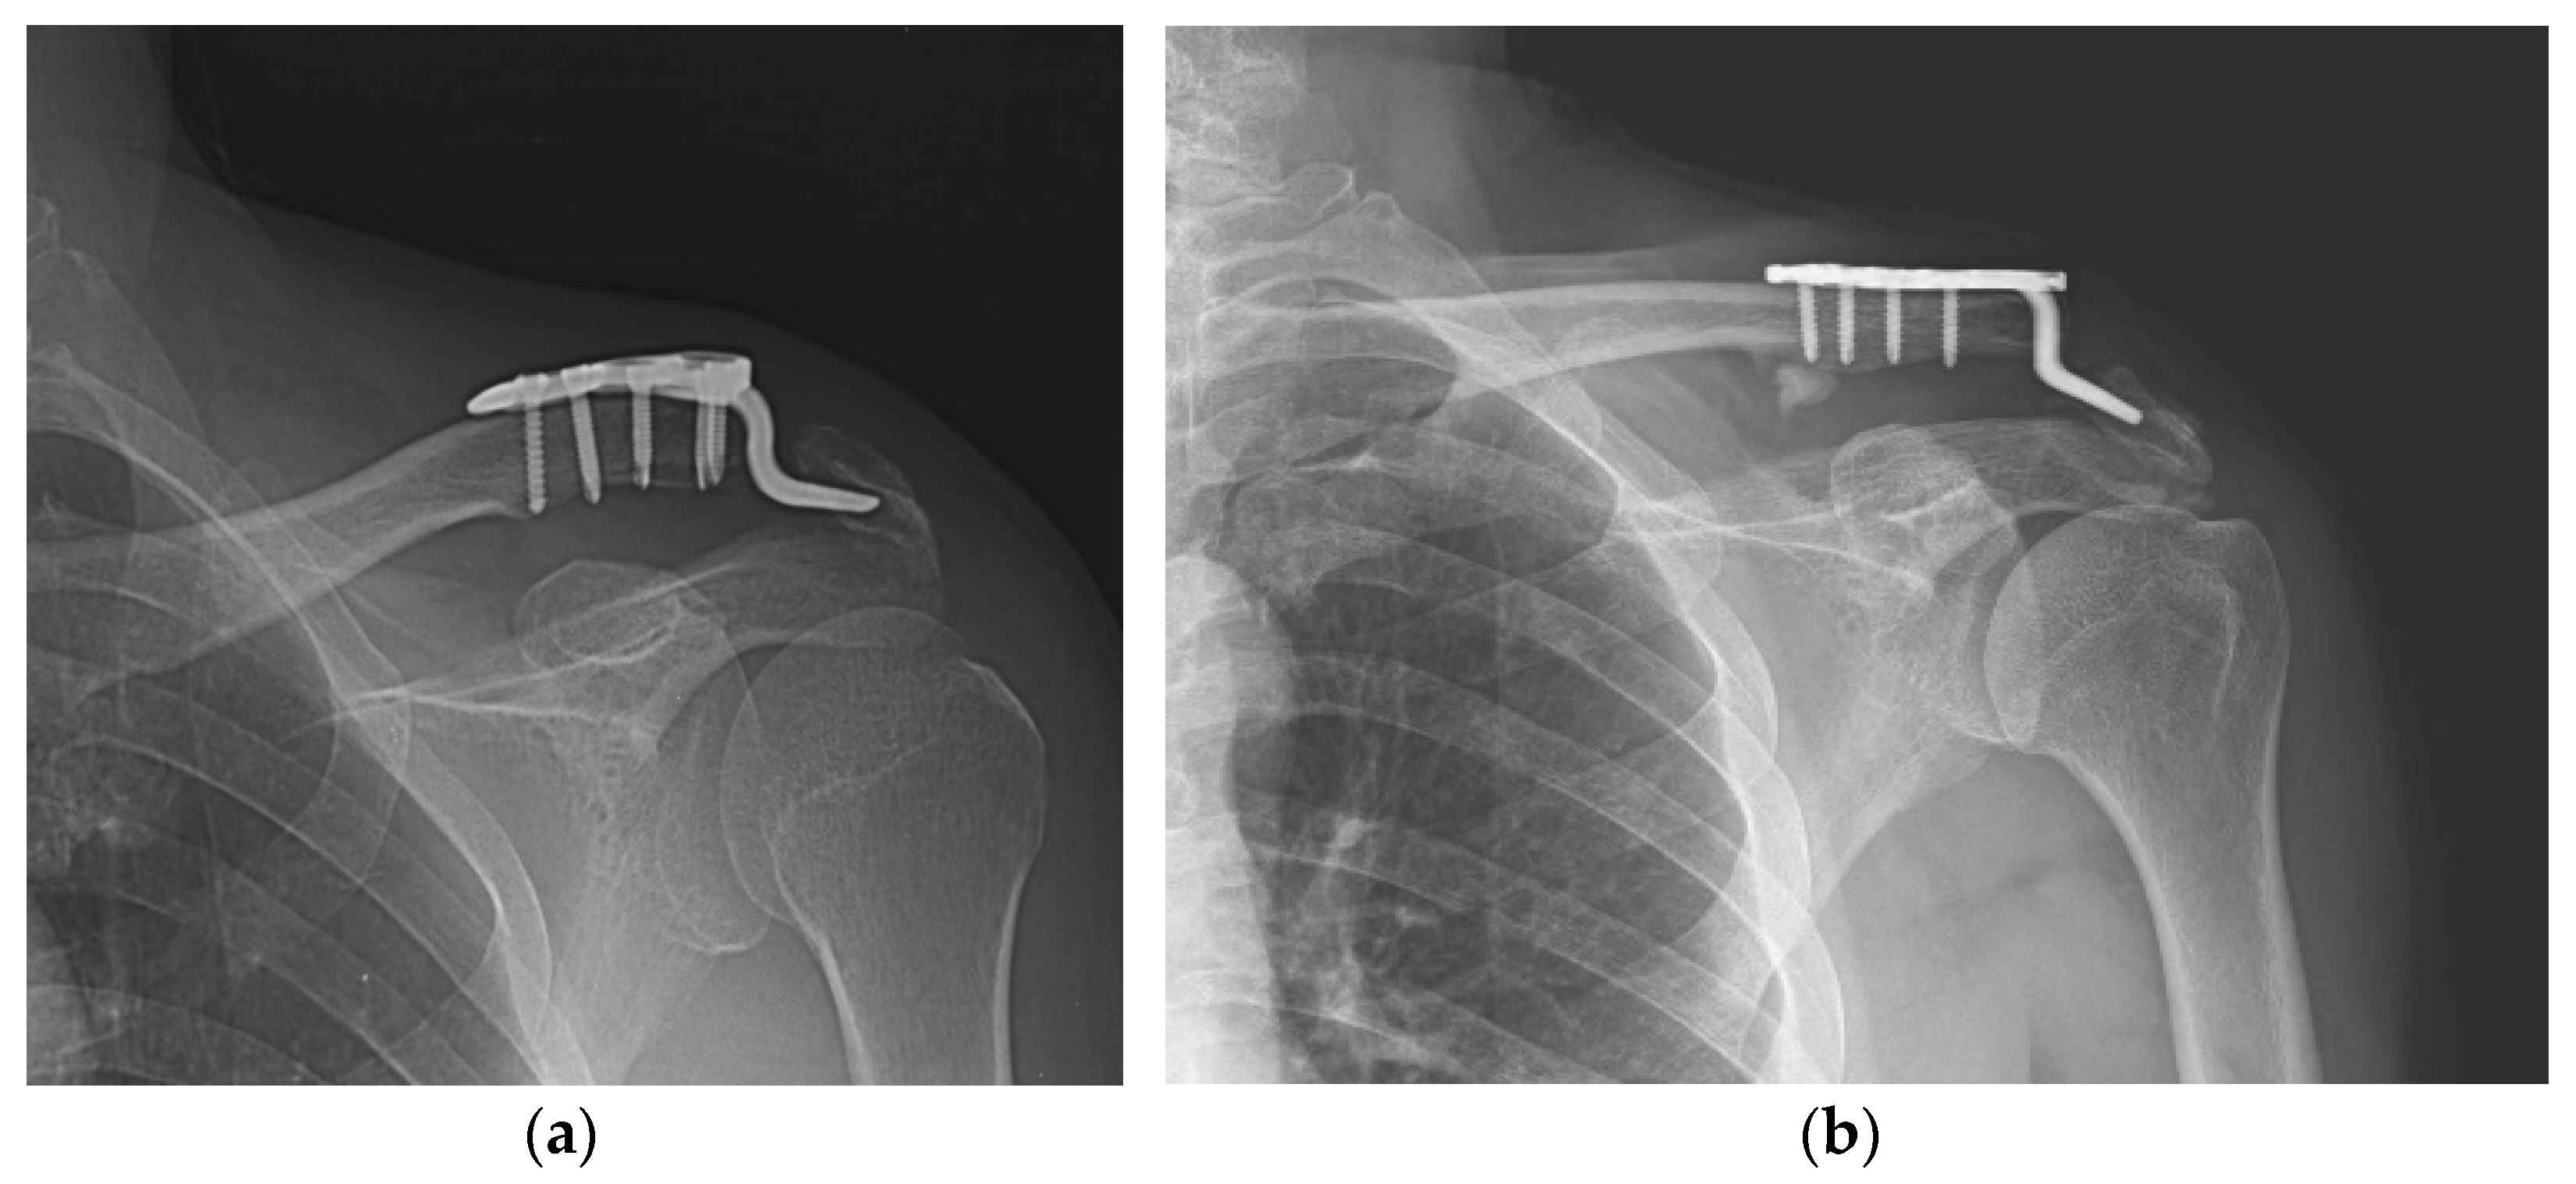

Varying degrees of subacromial erosion occurred in all patients, and acromial fracture occurred in one case in the DCF group and seven cases in the ACD group (Figure 2 and Figure 3). Five (6.7%) cases showed incomplete union and one (1.3%) case showed peri-implant stress fracture in the DCF group (Figure 4 and Figure 5). Four of the five cases of incomplete union showed fracture union without additional surgery during the follow-up period, and one case did not heal at the final follow-up, although the patient did not show any discomfort with non-union (Figure 6). The peri-implant fracture healed with conservative management before plate removal. LOR was observed in nine patients with ACD. Before removing the hook plate, LOR occurred in six patients with ACD. Among these six patients, five showed acromial fracture and one showed serious subacromial erosion (Figure 7). After removing the hook plate, LOR occurred in three patients during the follow-up period. However, none of these patients with LOR among patients with ACD showed tenderness on the acromioclavicular joint or pain during the follow-up period. Regarding acromial fracture, one (1.3%, 1 of 36) case was observed in the DCF group and seven (8.3%, 7 of 33) cases were noted in the ACD group (Figure 4). There was no difference in the incidence of acromial fracture between patients with DCF and ACD (p = 0.066). All eight patients had fracture union without additional surgical treatment during the follow-up period.

Figure 2. Acromial bony erosion. Varying degrees of bony erosions re observed in terms of eroded size and depth, which can be identified after plate removal.

Figure 3. Acromial fracture. (a,b) Acromial fracture may be developed by frictional movement between the hook and the acromion; (c,d) fracture healing is shown without any additional procedure.